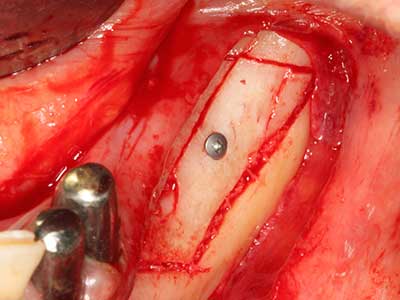

Bei der Knochenblockentnahme zeigen sich weitere Vorteile für die Piezochirurgie: Neben der bereits beschriebenen hohen Präzision bei der Osteotomie stellt sich gerade die Verwendung der dünnen Sägespitzen als besonders materialschonend heraus. Bei der Verwendung insbesondere von Lindemannfräsen sind mit deutlich höheren Entnahmeverlusten durch die dickere Instrumentenspitze zu rechnen (Lakshmiganthan, Gokulanathan et al. 2012). Die insbesondere bei retromolar entnommenen Blocktransplantaten notwendige basale Abtrennung wird durch speziell hierfür vorgesehene rechtwinklige Sägen erleichtert, so dass die Piezochirurgie als präzises, übersichtliches und sicheres Verfahren zur retromolaren Knochenblockgewinnung angesehen wird (Happe 2007) (Abb. 1-12).

Wie sich in der Vergangenheit gezeigt hat stellt prinzipiell jeder knochenchirurgische Eingriff eine mögliche Indikation für die Piezochirurgie dar. So lässt sich die Präparation des mobilen Segmentes bei der Distraktionsosteogenese (Abb. 23-25) und der Sandwichosteotomie mit speziellen Ansätzen bewerkstelligen, ohne die für den Erfolg beider Techniken essenzielle Blutversorgung des krestalen Anteils zu gefährden (Gonzalez-Garcia, Diniz-Freitas et al. 2008).